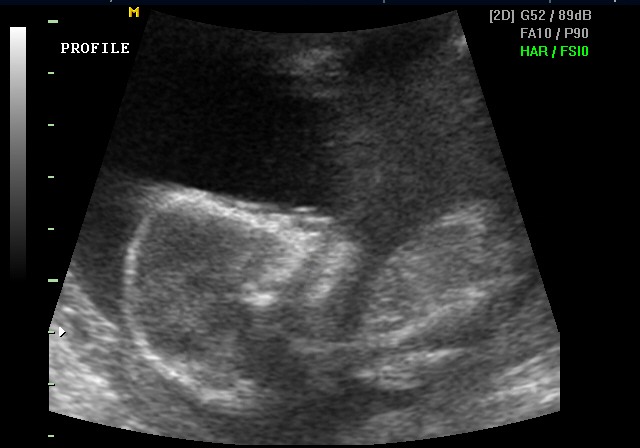

Ultrasound — Kennedy's profile, May 23, 2005

Profile — May 23, 2005